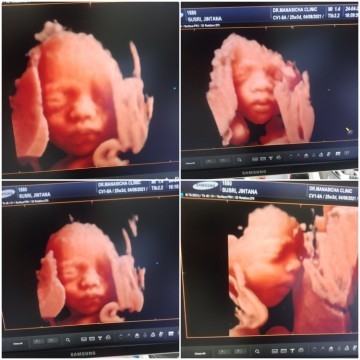

ภาพซาวด์4มิติ

ขอดูภาพซาวด์4มิติ ของแม่ๆท่านอื่นหน่อยคะ บ้านนี้ซาวด์ปัยน้องยิ้มเล่นไปด้วย ให้ทายว่าน้องเปนผญ.หรือผช.😊

28wผู้หญิง😊

26w ลูกสาวคะ

25w ผญ ค่ะ